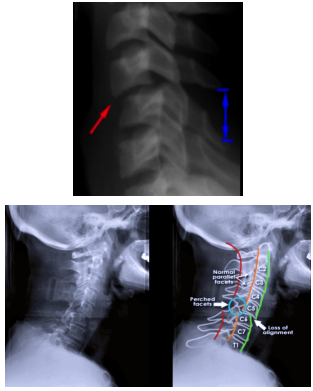

Luxação traumática

• Ocorre perda do alinhamento vertebral anterior, vertebral posterior, espino-laminar, espinhal posterior e das facetas (empoleiramento facetário)